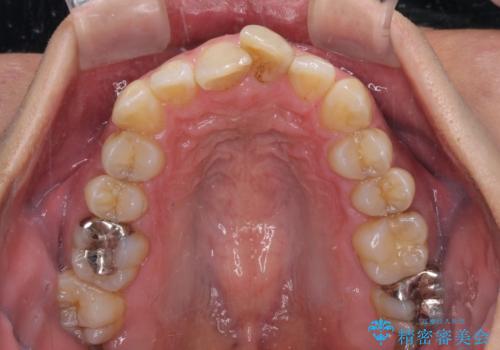

- 前歯のデコボコを気にして来院された患者様です。

下顎前歯のデコボコが特に強く、治療を早く終えることを考えるとワイヤー装置がお勧めですが、ワイヤー装置の異物感は避けたいのでインビザラインを希望されていました。

インビザラインで治療を行うか、ワイヤーで治療を行うかずっと悩んでいらっしゃいましたが、早く終わらせることを優先してワイヤー装置にて治療を行うこととしました。

下顎にワイヤー装置を装着し、暫くしたところでやはりインビザラインにて矯正治療をしたいとのことで、インビザラインに切り替えました。

短い期間でしたがワイヤー装置を使用したことでデコボコが解消されたため、インビザラインの比較的短い期間で矯正治療を行うことができました。